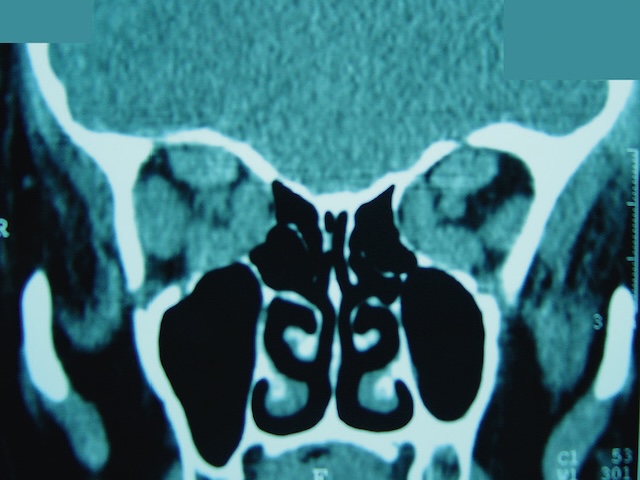

L’imagerie est essentielle pour mieux comprendre le mécanisme de l’orbitopathie. Le scanner et l’IRM sont complémentaires (fig. 21.8). Ils peuvent conforter le diagnostic d’exophtalmie, et objectiver les rapports entre les nerfs optiques et les muscles à l’apex orbitaire en cas de neuropathie optique.

Cette coupe coronale de tomodensitométrie met en évidence un épaississement significatif des muscles oculomoteurs, en particulier les muscles droits inférieurs et médians. Leur volume anormalement augmenté réduit l’espace rétro-orbitaire et crée un contact étroit avec les nerfs optiques bilatéralement. On note que les structures osseuses orbitaires sont bien délimitées, sans lyse apparente, tandis que les sinus para-nasaux, bien visibles au centre de l’image, sont aérés. L’aspect évoque une orbitopathie thyroïdienne active, avec risque de neuropathie optique compressive en raison de l’encombrement postérieur de l’orbite par les muscles élargis.